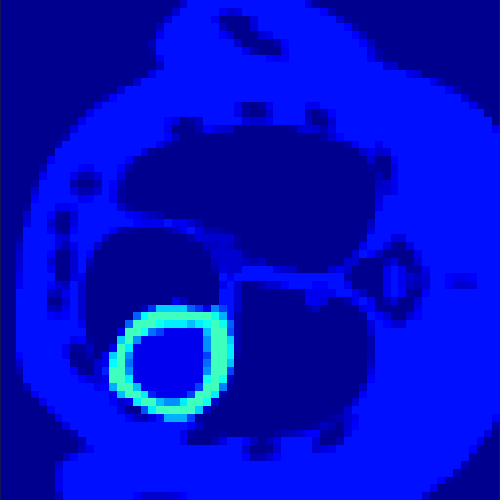

5.2 Monte Carlo Simulation

In order to test the behaviour of the proposed method in a more realistic, random-based test case, we performed a Monte Carlo simulation for dynamic SPECT imaging. First, we created a simple image phantom consisting of an outer and two inner circles which represents the structure of the region of interest (see figure 8(a)). Within those regions we assumed concentration curves over a time period of 90 time steps as displayed in figure 8(b). Based on the tracer intensity in an image frame at each time step, we created a variable number of random decay events (where the number is proportional to the average concentration in one pixel in the whole image frame per time step) with a probability proportional to the concentration in every subregion. They are detected by a virtual double head gamma camera rotating around the patient by 46 degrees per time step, which consists of 374 detector bins. Every simulated decay event is projected onto the scanner and counted by the corresponding detector bin.

Based on the sinogram data we applied the proposed algorithm in order to reconstruct the original image sequence. The results for both test cases are shown in figure 10.

As one can see, the method is able to reconstruct the regions properly, even in case of a low count number. Within a number of iterations (average of 100 outer and 10000 inner iterations), the algorithm presents a reasonable reconstruction of the region of interest and the corresponding regional tracer concentration curves. Here, the parameters were not optimized as in the case of the synthesized data sets in the previous section, but kept fixed as , and . With futher optimized parameter values one could possibly provide even better results.